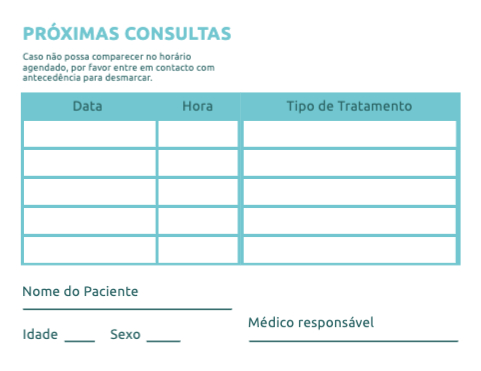

Escolher um template (Cartões de Visita com Dobra)

VoltarModelos de Cartões de Visita com Dobra

Explore diferentes estilos e modelos de cartões de visita com dobra. Escolha o design que melhor representa o seu negócio e personalize-o facilmente no nosso editor de design online.